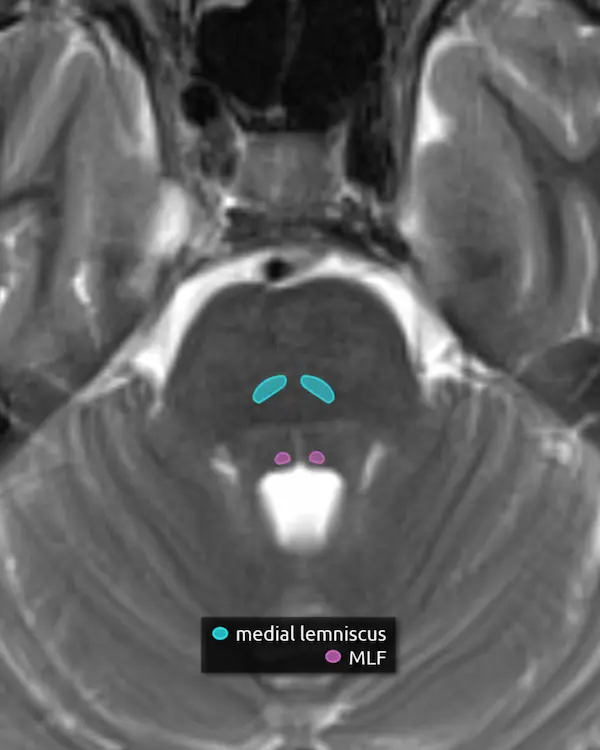

5. Medial lemniscus

The medial lemniscus is an ascending sensory pathway that spans the entire brainstem, originating at the nucleus gracilis and cuneatus (see level 5) in the medulla and ending at the primary sensory nucleus of the thalamus: the ventral posterolateral nucleus (VPL). It begins medially in the medulla and becomes more lateral at the level of the midbrain, located in close proximity to the substantia nigra. It is responsible for vibration sensation, fine touch, and proprioception.

Lesions involving the medial lemniscus may cause contralateral loss of vibration sensation and joint position sensation on physical exam with symptoms of numbness and paresthesias.

6. Medial longitudinal fasciculus (MLF)

The MLF is an ascending and descending pathway responsible for coordinating eye movements. It connects all of the cranial nerve nuclei that innervate the extraocular muscles (CN III, IV, and VI) as well as the vestibulocochlear nuclei (CN VIII). The MLF spans the entire brainstem, however lesions producing visual symptoms will probably be in the midbrain or pons.

There are characteristic syndromes that result from damage to the MLF, most commonly internuclear ophthalmoplegia (INO) or INO-plus syndromes. A common clinical scenario is a patient with multiple sclerosis who develops a demyelinating lesion along the MLF in the midbrain or pons and presents with bilateral INO.